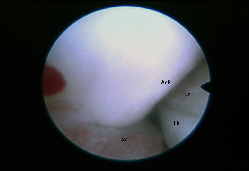

Arthroskopie des Hftgelenkes: vorderer Rand der Pfanne (Ac) und Oberschenkelkopf (FK) mit Anheftungen der Schleimhaut (Sy)

Arthroskopie Hftgelenk oberer Pfannenrand

Arthroskopie Hftgelenk: Oberer Pfannenrand (AcR), Anheftung der Kapselschleimhaut (Sy), Oberschenkelkopf (FK) und Band (LT)